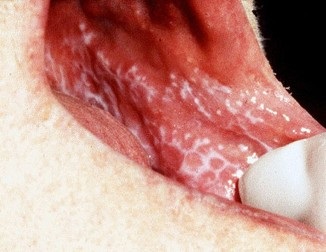

În cavitatea bucală, CPL este prezentat nu ca pielea și clasic caracterizată prin formarea de papule alb sau gri miliare grupate ca linii, cercuri și rețele care formează un model distinctiv pe mucoase care seamănă cu dantelă, inele și dungi pe mucoasa bucală, și într-o măsură mai mică pe limba, gingii, cerul gurii și a buzelor.

La papule albicioase mucoase nemodificate nu poskablivanii îndepărtate atunci când se formează modelul de plasă.

lichen plan, o formă tipică:

Papule pe partea dorsală a limbii sub formă de plăci îmbinate.

lichen plan, forma eroziv:

Pe obraz mucoasei papule albe, care fuzionează în tiparul de plasă, împotriva căreia eroziunea determinată.